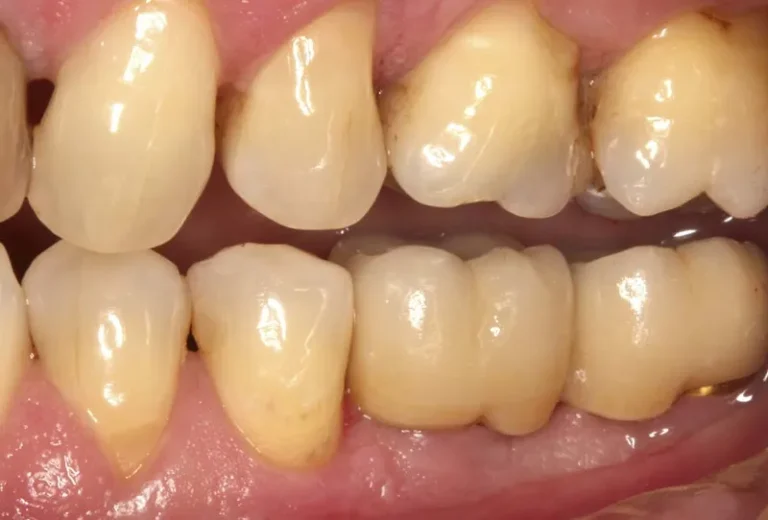

Los implantes dentales y los dientes naturales presentan características únicas que los diferencian tanto en estructura como en funcionamiento. Mientras los dientes naturales cuentan con ligamentos periodontales que proporcionan sensibilidad y capacidad de adaptación, los implantes se integran directamente al hueso mediante oseointegración. Esta distinción fundamental influye en aspectos como la sensibilidad a la temperatura,…